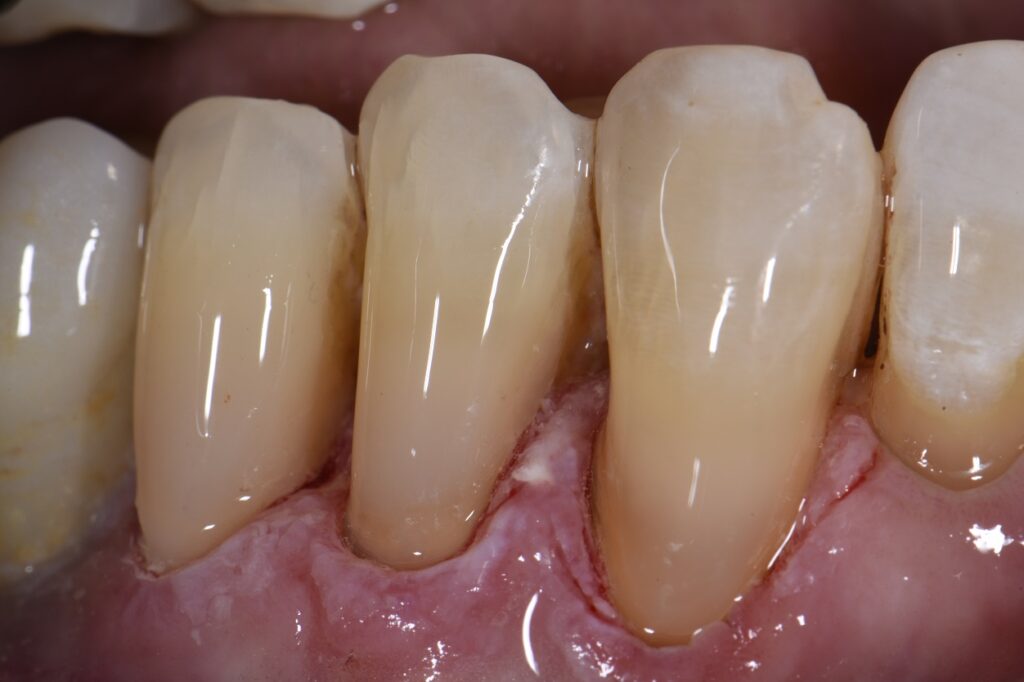

Small Sensitive Root Abrasion Lesions What Is Abrasion In Dental    abrasion is the result of repeated contact between a tooth and something hard, like teeth. However, bigger problems arise when your bite is out of alignment, often causing more friction in places less prepared for it. This wears away the enamel, the outer layer of the tooth, making it more susceptible to. So, when two or more teeth come. What Is Abrasion In Dental.